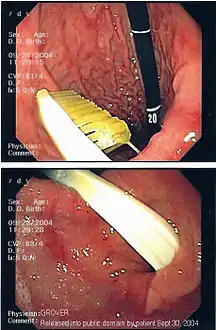

![]() تنظير داخلي للقناة الهضمية تظهر وجود جسم غريب (فرشاة أسنان) تنظير داخلي للقناة الهضمية تظهر وجود جسم غريب (فرشاة أسنان) | |